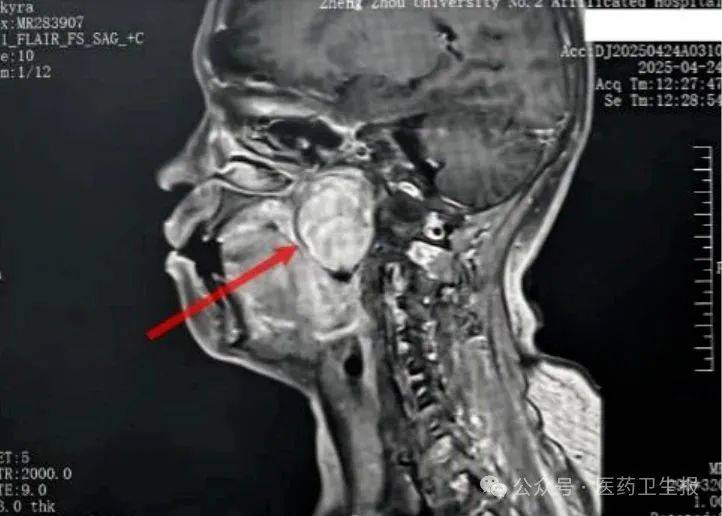

患者张某因右侧面部感觉异常、吞咽食物时咽部异物感到当地医院就诊,被查出咽部右侧深部间隙内存在直径6厘米~7厘米的巨大肿瘤。 由于该区域解剖结构复杂,张某初诊时被误诊为鼻咽癌。因治疗效果不佳,张某被转